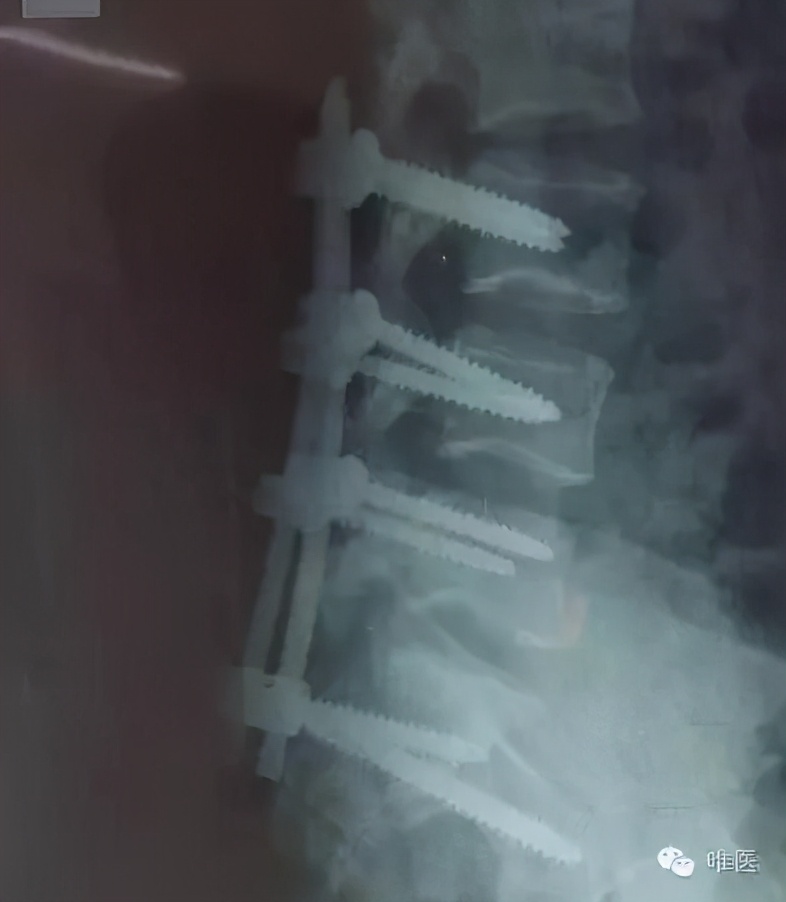

术中直接复位有些困难,部分咬除骶一和骶二的椎板,探查见硬脊膜是完整的,通过髂腰螺钉的提拉和杠杆作用一点一点复位。

▼ 术后照片